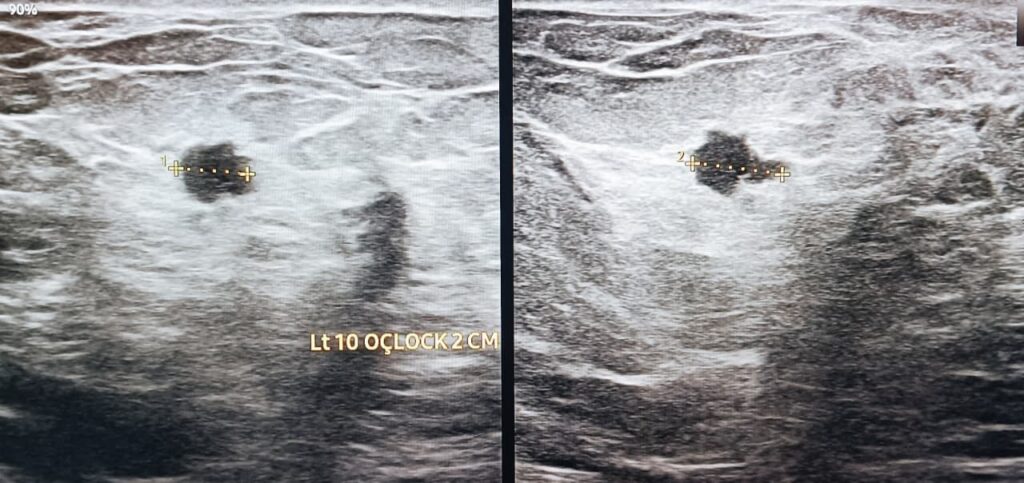

A highly suspicious lesion in the same breast was noted medial to the nipple. It was only about less than two centimetres in size, but had all the malicious sonographic characteristics.

The sonographic impression was that of a breast malignancy.

The patient was advised to go through further imaging and histopathological investigations to confirm exact nature of the lesion.